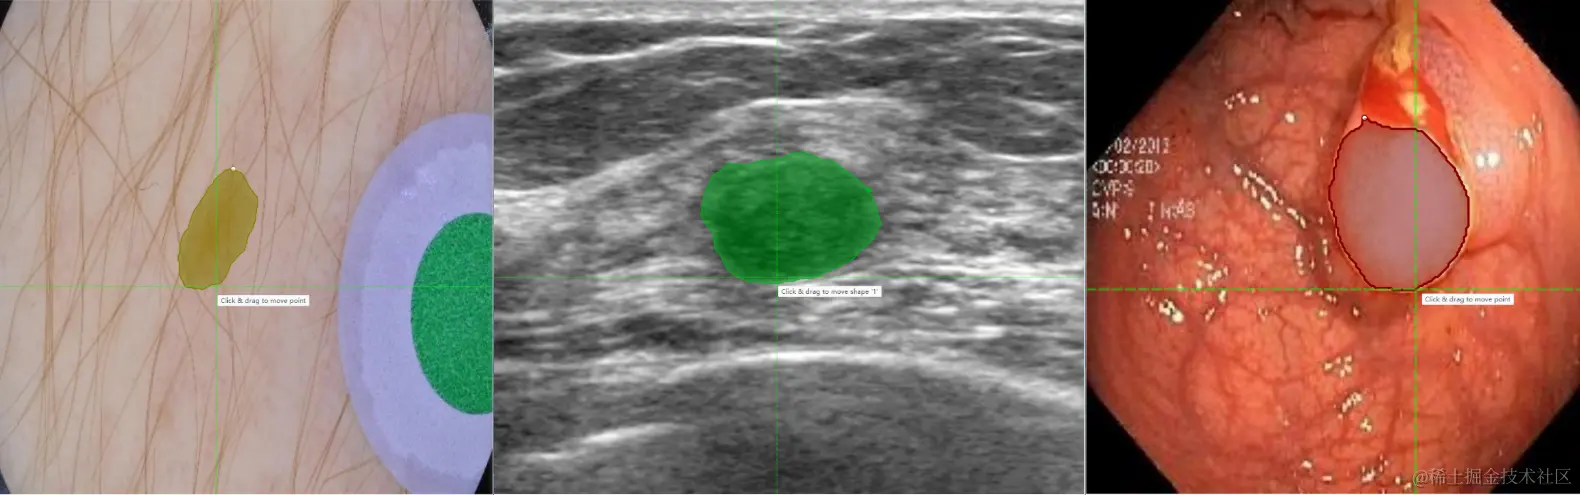

更进一步地,针对医学图像场景,X-AnyLabeling中同样提供了多种基于 SAM 微调的高精度模型,包括:

• SAM-Med2D: 通用医疗图像分割一切模型;

• LVM-Med ISIC SAM:皮肤病灶分割一切模型;

• LVM-Med BUID SAM:超声乳腺癌分割一切模型;

• LVM-Med Kvasir SAM:结直肠息肉分割一切模型;